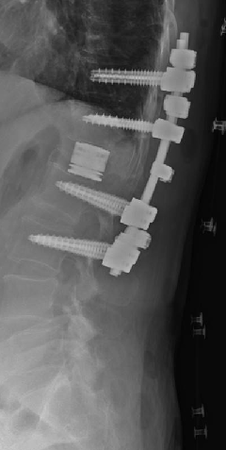

術前MRIでは腰椎正面で弯曲を認めています。多椎間の脊椎固定術を施行し症状が改善しています。

変性側弯症の患者さんで、難治性の腰痛と夜間も続く坐骨神経痛のために日常生活が困難でした。下位腰仙椎の多椎間で変性、側弯変形を認めます。

腰仙椎前方後方同時固定術による側弯変形の矯正、神経の除圧を行いました。悩んでいた腰痛がなくなり、坐骨神経痛が無くなったため夜間も穏やかに眠れるようになりました。